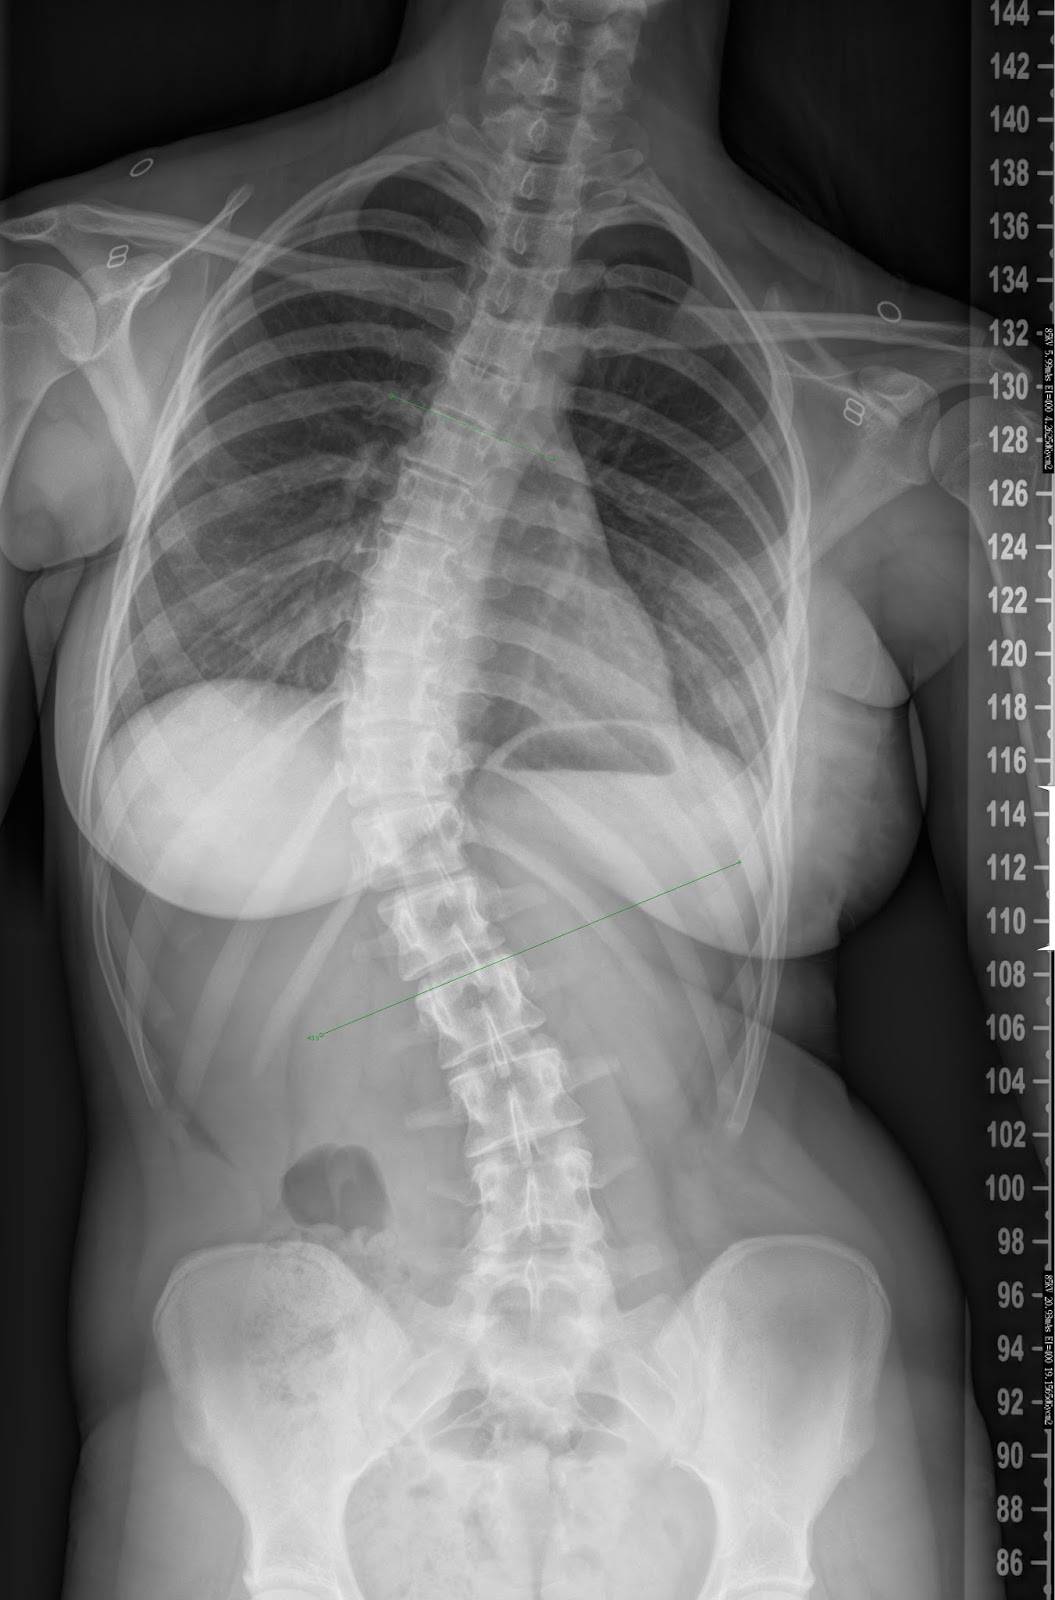

Bei einer Skoliose handelt es sich um eine seitliche Verkrümmung der Wirbelsäule, die mit einer Verdrehung der Wirbelkörper einhergeht. Außerdem kommt es auch zu einer unnatürlichen Drehung der Wirbelsäule in sich. Sie treten typischerweise im Wachstumsalter auf (Skoliose), das Korsett hilft daher nur bei Kindern während der Wachstumsphase. Die Heilmittelrichtlinie stellt seit dem 1. sloopy Seiten-Eigentümerin Beiträge: 6123 Registriert: Do, .Die Skoliose kann als besonders frühe Form im Säuglingsalter auftreten – hier spricht man von einer Säuglingsskoliose. Bei der Skoliose zeigt die . Die Symptome sind vielfältig – . Sie führt zu einer mehr oder weniger deutlich sichtbaren Fehlhaltung.Die Krankenkasse in Österreich zahlt eine Skoliose Matratze vollständig oder teilweise, wenn man ein Attest vom Arzt vorlegen kann und die Matratze im Hilfsmittelverzeichnis angegeben ist. Die durch das Korsett aufgebauten Druckkräfte wirken gegen die Rotation und Verkrümmung der .Tätigkeit: Facharzt Für Orthopädie

Mein Orthopäde, den ich gewechselt habe hat mir gesagt ich hätte eine Skoliose (meine Wirbelsäule sieht von hinten aus wie ein S).Es gibt verschiedene Möglichkeiten eine Skoliose einzuteilen: 1.deWird eine Skoliose im zunehmenden Alter immer schlimmer?forum.Als Skoliose wird eine fixierte, seitliche Verbiegung der Wirbelsäule bezeichnet, wobei das Rückgrat des Menschen nicht nur seitlich ausgebogen ist, sondern auch weitere Komponenten wie Torsion und Rotation enthält (dreidimensionale Verkrümmung).

Um eine vorherige Anmeldung wird gebeten, unter Tel.Fragen und Antworten rund ums Korsett.Wie macht sich eine Skoliose bemerkbar? Eine leichte Form der Skoliose ist äußerlich nicht erkennbar, sie kann sich aber bei Betroffenen durch Rückenschmerzen und Verspannungen bemerkbar machen. Falls andere Erkrankungen wie Knochenbrüche, Krebs, Entzündungen und Nervenschäden im Bereich der Wirbelsäule für Ihre chronischen Schmerzen verantwortlich sind, werden diese zuerst behandelt. Die Wirbelsäule bei Patienten mit einer Skoliose stellt sich in einer S-Form dar, wenn man hinter dem Patienten steht. Buchen Sie einen Termin.Wird bei Ihnen ein Haltungsschaden festgestellt, stimmt Ihr Arzt die Therapie individuell auf die zugrundeliegenden Ursachen ab.Schlagwörter:Cobb-WinkelSkoliose Korrigieren Herzlich willkommen, DSN Deutsches Skoliose Netzwerk & Team.ich bin jetzt 23 Jahre alt und habe im Schrank ein Röntgenbild von meinen Rücken, als ich 14 war.Welcher Sport ist möglich mit Skoliose?Menschen mit Skoliose sollten nicht auf Bewegung verzichten. Skoliose-Korsett.deEmpfohlen basierend auf dem, was zu diesem Thema beliebt ist • Feedback

Unter Skoliose versteht man eine dreidimensionale Deformierung der Wirbelsäule.Wie fortgeschritten eine Skoliose ist – das beurteilen Fachleute anhand des Krümmungsgrades. Eine behandlungsbedürftige Skoliose liegt vor, wenn der sogenannte Cobb-Winkel mehr als zehn Grad beträgt.